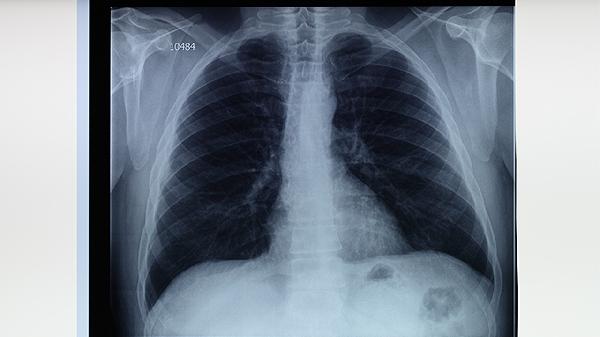

肺结核治疗药物如异烟肼片、利福平胶囊等可能对生殖细胞或胎儿发育产生影响,停药后需等待药物完全代谢。抗结核药物半衰期较长,部分成分可能在体内残留数月,过早怀孕可能增加胎儿畸形或发育异常的风险。患者需完成全程规范治疗并复查痰培养、胸部CT等确认病灶稳定,确保无活动性结核杆菌残留。若合并肝肾功能损伤,需延长等待期至肝功能指标恢复正常。医生会根据个体情况调整备孕时间,期间建议采取可靠避孕措施。

备孕前应进行结核菌素试验、胸部影像学复查,排除复发可能。女性需补充叶酸片预防神经管缺陷,男性应避免吸烟饮酒。妊娠期间若出现低热、咳嗽等症状需及时排查结核复发。哺乳期患者需告知医生用药史,避免通过乳汁传递药物成分。定期监测母婴健康状况,必要时在感染科与产科联合指导下进行干预。